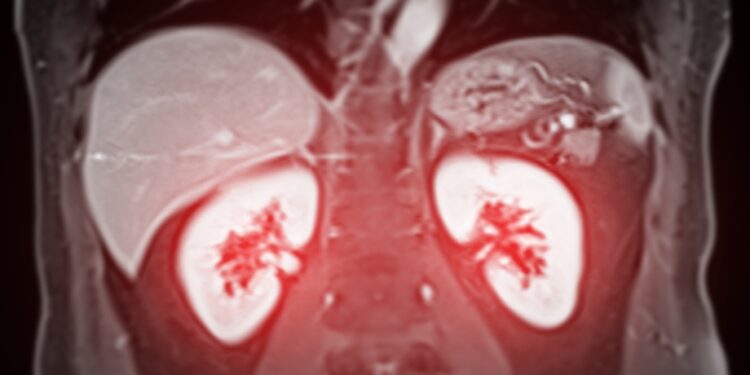

Kas yra inkstų cista?

Inkstų cistos (dar vadinamos inkstų ar renalinėmis cistomis) – tai apvalios, ploną sienelę turinčios ertmės, pripildytos skaidraus skysčio. Dažniausiai jos formuojasi su amžiumi – cistos atsiranda inksto paviršiuje arba jo vidinėse dalyse, vadinamose nefronais.

Inkstai mūsų organizme veikia kaip natūralūs filtrai: nefronai šalina iš kraujo perteklinį vandenį ir nereikalingas medžiagas, kurios vėliau pašalinamos su šlapimu. Cistos dažniausiai nė kiek netrukdo inkstų veiklai. Jos gali būti mažesnės nei 5 cm, tačiau kartais toliau auga arba išlieka nepakitusio dydžio. Vienas žmogus gali turėti tik vieną arba keletą cistų abiejuose ar viename inkste.